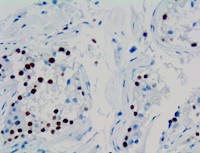

MAGEC2 is used to distinguish Seminomas from Embryonal Carcinomas. MAGEC2 marker is a tool for the differential diagnosis of testicular germ cell tumors. Immunohistochemical expression of MAGEC2 has a consistent and strong nuclear signal in 100% of non-neoplastic germ cells and Intratubular Germ Cell Neoplasia of Unclassified type (IGCNU). The staining is very strong in immature forms of spermatogonia and spermatocytes, but weakens gradually with more mature forms like spermatids. No MAGEC2 expression was found in normal mature sperm cells. In Seminomas, MAGEC2 is expressed in 238 of 254 cases. From the other germ cell tumor components: 5 of 51 yolk sac tumors (10%) and 1 of 10 choriocarcinomas (10%) were positive, but none of the Embryonal Carcinomas or Teratomas had any nuclear expression of MAGEC2 marker. MAGEC2 can be identified as a sensitive marker to differentiate Seminomas from other types of Germ Cell tumors.